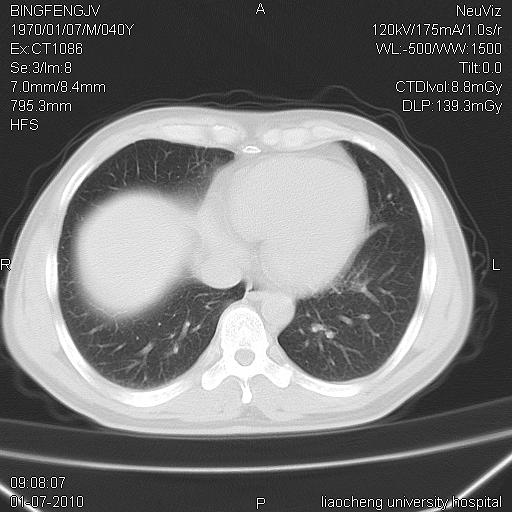

炎症性病灶,继发性改变。

考虑左肺上叶近胸膜下炎症并肺气囊形成。

炎症,大部吸收。